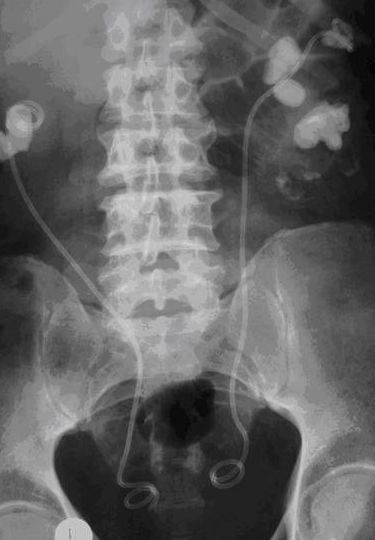

Для длительного дренирования ВМП используют специальный мочеточниковый катетер-стент с двумя завитками. Верхний завиток устанавливают в лоханке, а нижний — в мочевом пузыре; таким образом, катетер не смещается при изменении больным положения тела и практически не препятствует ему вести активный образ жизни (рис. 6-2). С помощью таких катетеров-стентов можно дренировать мочевыводящие пути человека до 12 мес.

Обзорная рентгенограмма органов мочевой системы. Мочеточниковые стенты дренируют верхние мочевыводящие пути с обеих сторон при двусторонних коралловидных камнях.